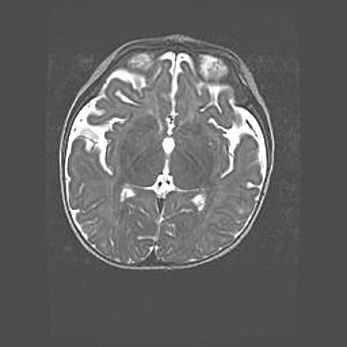

Множественные кисты обоих полушарий головного мозга, наибольшая из них в правой затылочной области. Ассиметричная атрофическая гидроцефалия.

Возраст: 7 месяцев

Вес: 5660 г

Пол: мужской

Окружность головы: 41,5 см

Срок гестации: 28-29 недель

Кисты головного мозга развиваются в результате многоочаговых некрозов вещества мозга и возникают вследствие перенесенной перинатальной инфекции, менингитов, энцефалитов, асфиксии, родовой травмы, расстройств мозгового кровообращения различного генеза. Образованию кист в веществе головного мозга плодов и новорожденных способствуют такие факторы, как высокое содержание в нем воды, недостаточная (или отсутствие) миелинизация и слабая астроглиальная реакция на повреждение.

Кисты могут сочетаться с гидроцефалией и другими поражениями головного мозга.